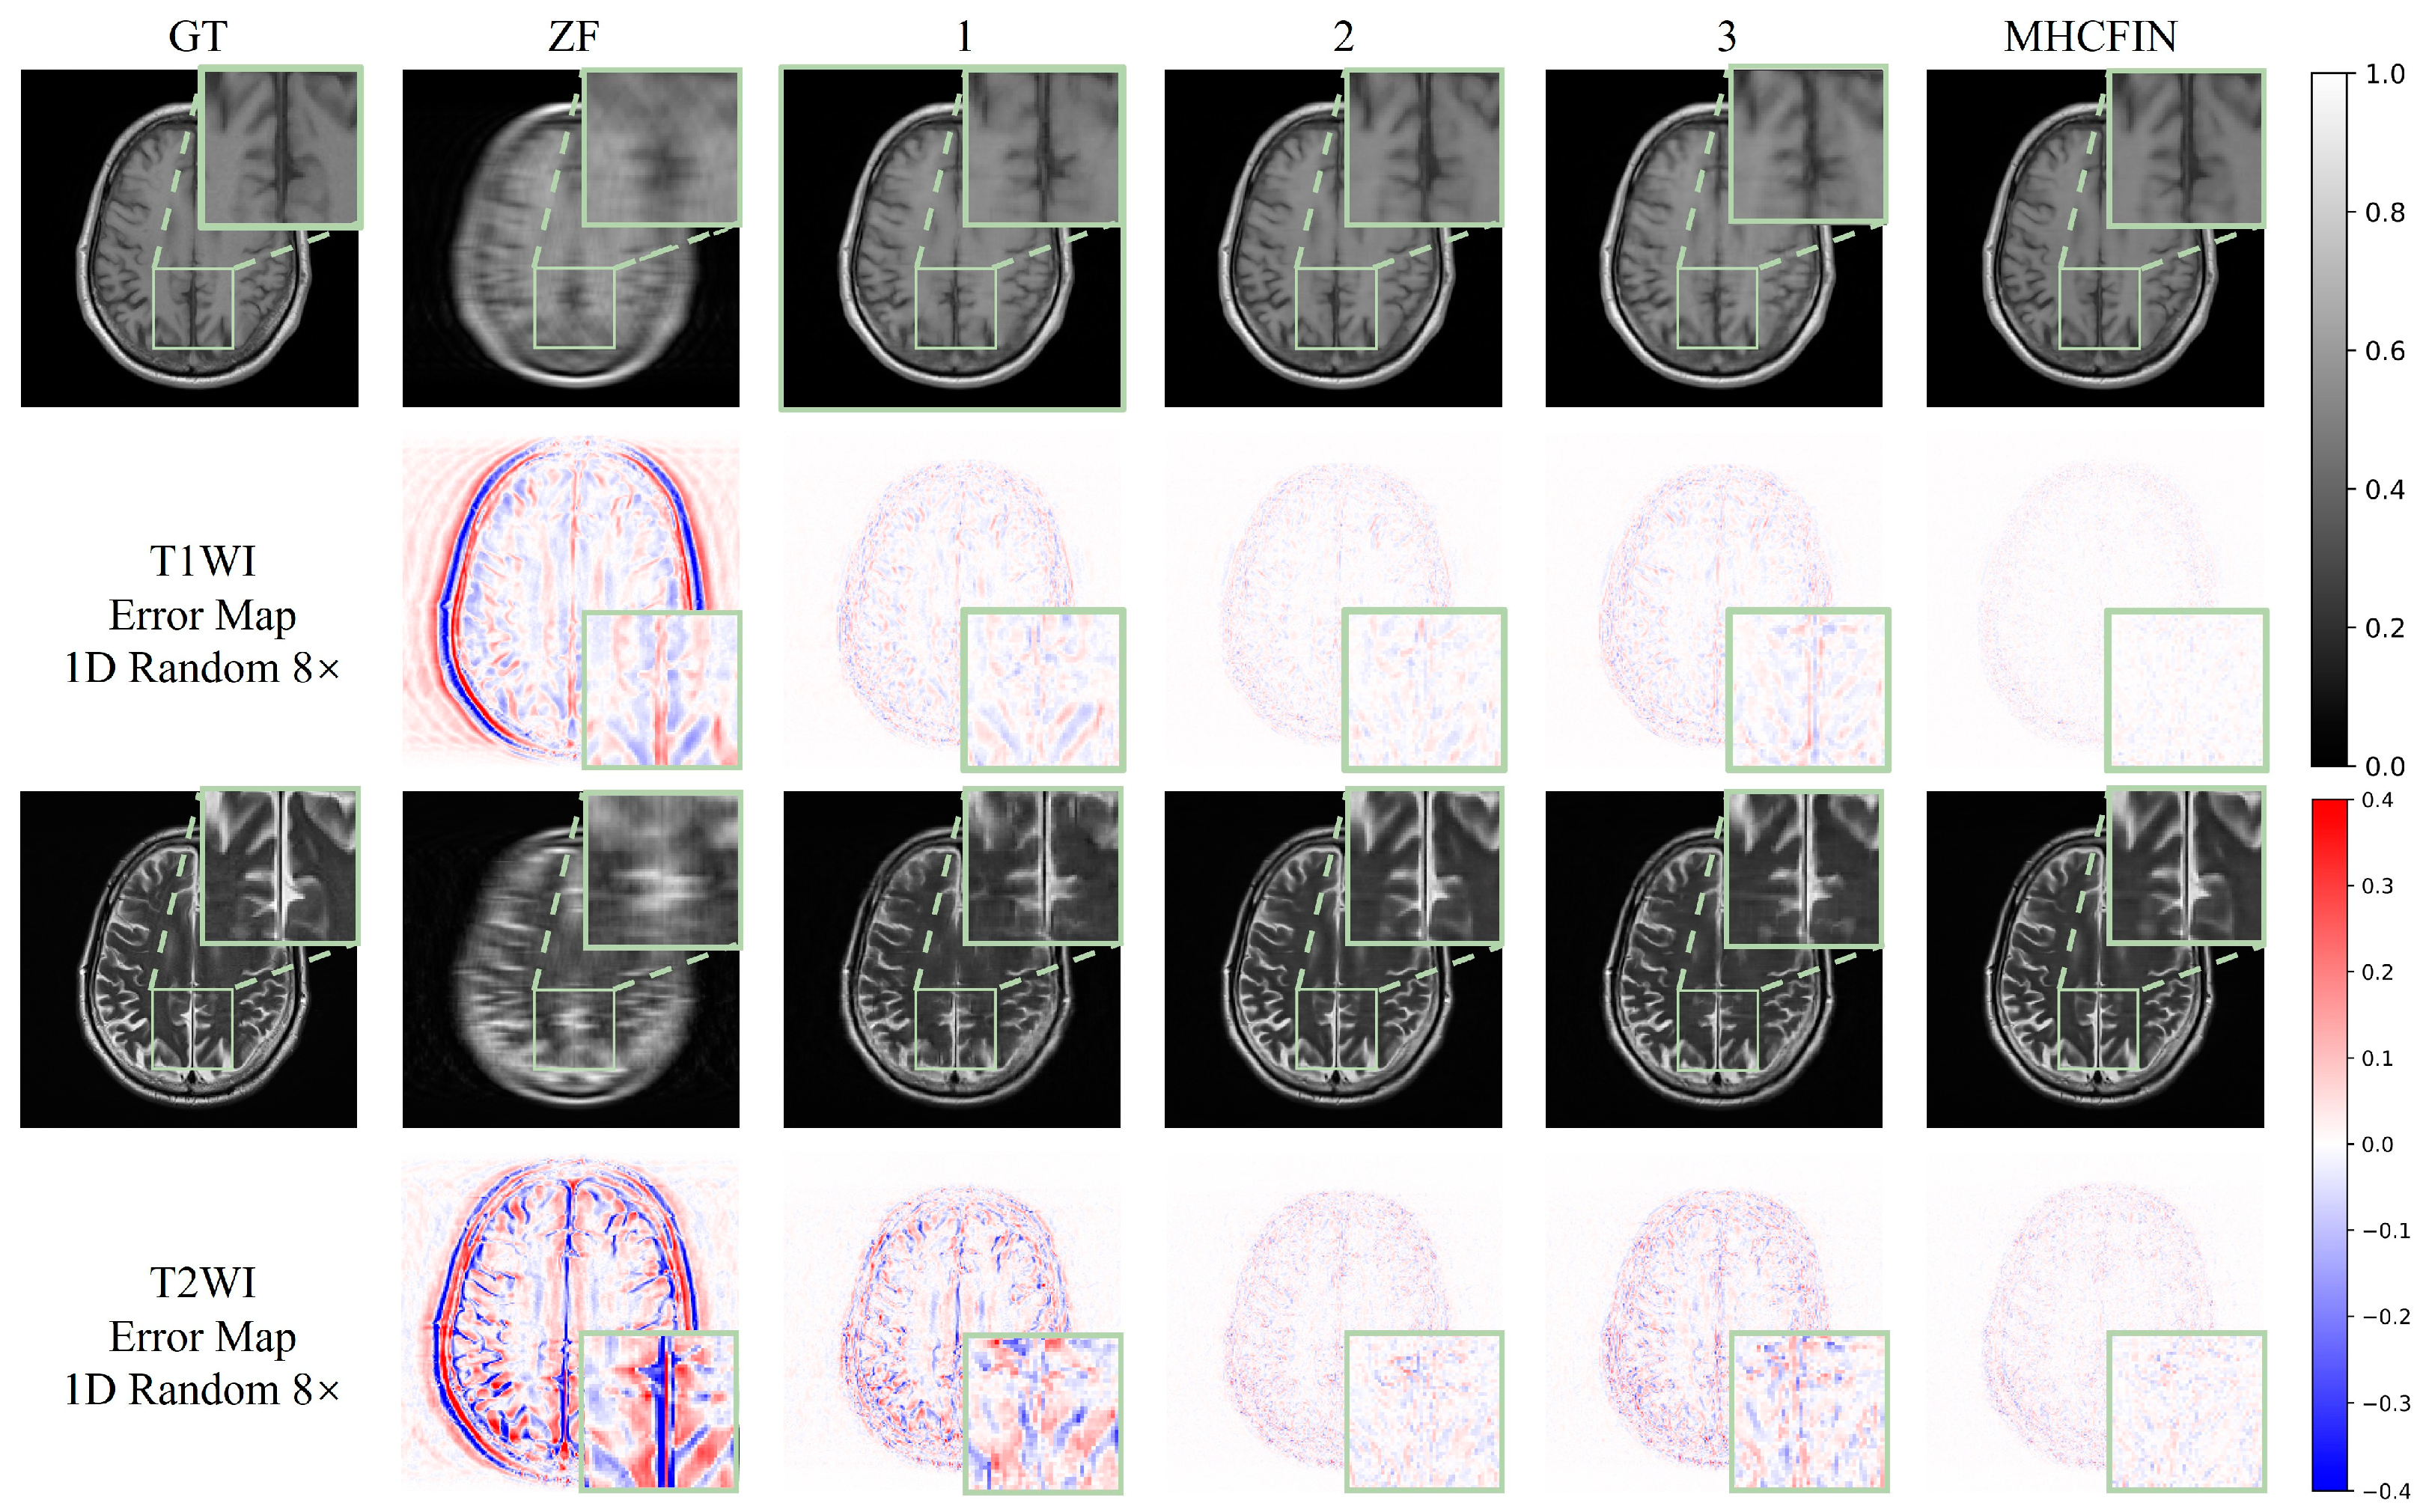

5.2. Qualitative Results

- Discussion on encoder and decoder based on residual multi-attention: To verify the efficacy of the key components in the proposed method, we evaluate three models in an ablation study. First, we evaluate the proposed residual multi-attention-based decoder–encoder model, in which we replace residual learning with traditional skip connections and remove the triple-attention mechanism. From the data in Table 4, we can see that, compared with configurations 1 and 2, without residual multi-attention (RMA), the PSNR of T1WI decreases by 2.974 dB and the SSIM decreases by 0.037; similarly, the PSNR of T2WI decreases by 5.964 dB and the SSIM decreases by 0.08. It can also be observed in Figure 12 that the reconstruction error of configuration 2 is reduced compared to configuration 1 which does not integrate any components, and the restored image details are clearer.

- Discussion on the multi-modal feature interaction module and single-modal feature fusion module: Since the multi-modal fusion interaction module and the single-modal feature fusion module are used jointly, we discuss their effects together in the ablation study. As can be seen from the data in Table 4, compared with configuration 1 without using these feature fusion technologies, configuration 3 has the PSNR of T1WI increased by 0.782 dB, SSIM increased by 0.005, and RLNE decreased with the help of multi-modal feature interactive learning by 0.006; the improvement of T2WI is more significant, as PSNR increases by 3.338 dB, SSIM increases by 0.052, and RLNE decreases by 0.052. Figure 12 also clearly shows that, after the introduction of MMFIM and SMFFM, the overall reconstruction error is reduced; especially, the improvement on T2WI is particularly obvious. Based on the introduction of RMA, the difference between MMFIM and SMFFM is particularly significant. By comparing configuration MHCFIN with configuration 2, it can be seen that the PSNR of T1WI has increased by 3.323 dB, and the PSNR of T2WI has increased by 2.01 dB. This result verifies the effectiveness of our proposed components, and when these components are used jointly, they can bring better results than when used alone. At the same time, learning complementary information between different modalities can also further improve the quality of reconstruction.

| Variant | RMA | MMFIM | SMFFM | fastMRI Brain | |||||

| ZF | × 1 | × | × | 22.572 | 0.646 | 0.300 | 21.764 | 0.673 | 0.310 |

| 1 | × | × | × | 33.599 | 0.902 | 0.074 | 27.261 | 0.856 | 0.164 |

| 2 | √ 2 | × | × | 36.573 | 0.939 | 0.053 | 33.225 | 0.936 | 0.083 |

| 3 | × | √ | √ | 34.381 | 0.907 | 0.068 | 30.599 | 0.908 | 0.112 |

| MHCFIN | √ | √ | √ | 39.896 | 0.964 | 0.036 | 35.235 | 0.948 | 0.065 |